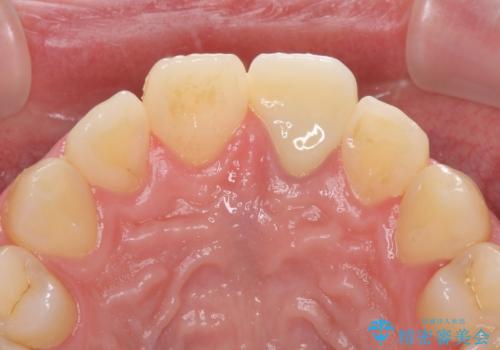

- 中学生の時にぶつけて以来、そのままにしていたところ前歯が変色してきたとのことで来院された患者様です。

レントゲン写真より、歯の中の神経組織が失活していることが分かったため、根管治療、ファイバーコアによる土台築製を行い、オーダーメイドタイプのオールセラミッククラウンにて補綴することとしました。

人目を気にすることなく話ができるようになり、患者様には大変満足していただきました。